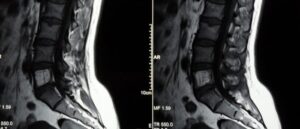

Гемангиома позвоночника

Если во время исследования у человека была выявлена гемангиома позвонка, не стоит впадать в панику и бояться, что это опасное заболевание. В большинстве случаев опухоль считается доброкачественной, и если она не вызывает болей и дискомфорта, никакого лечение не требуется. Но бывают случаи, когда происходит все наоборот, тогда стоит обратиться к врачу, который назначит лечение. Рассмотрим, …

Гемангиома по наследству

Медики не могут точно ответить передаются ли гемангиомы по наследству. Однако врачи уверены, что такое сосудистое образование надо контролировать и в неблагоприятных случаях удалять. Поэтому при обнаружении новообразования не надо медлить, а рекомендуется в ближайшее время пройти обследование, по результатам которого доктор назначит дальнейшие действия. Вероятность заболеть гемангиомой по наследству остаётся неизученным вопросом для учёных. …